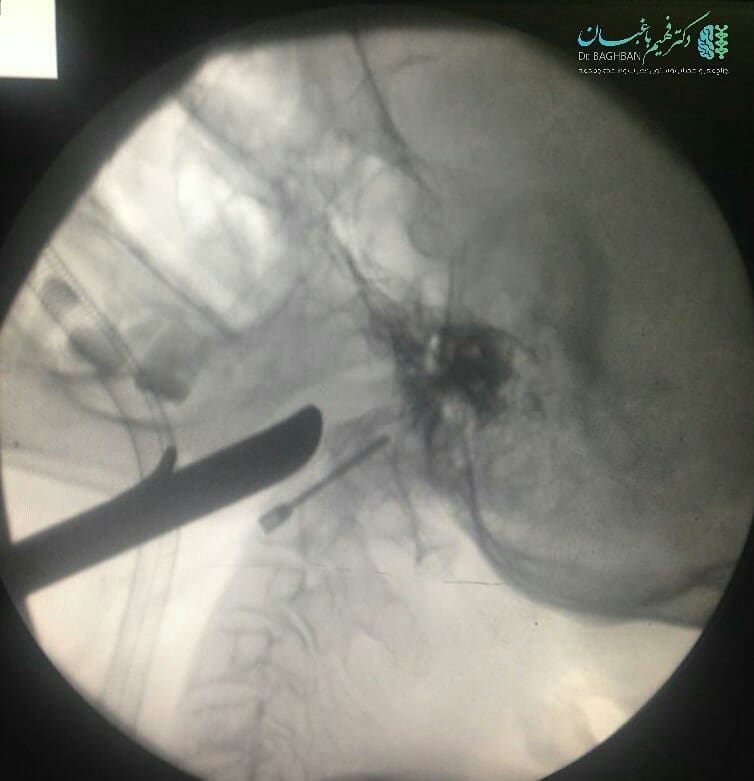

بیمار آقای ۲۹ ساله با شکستگی مهره دوم گردن (Odontoid Fx) می باشند که تصاویر حین جراحی و شکستگی را زیر مشاهده می نمایید. در این شیوه جراحی با قرار دادن یک پیچ در مهره شکسته بدون محدودیت حرکتی بهبودی کامل ایجاد می شود.

کارگذاری پیچ در مهره شکسته